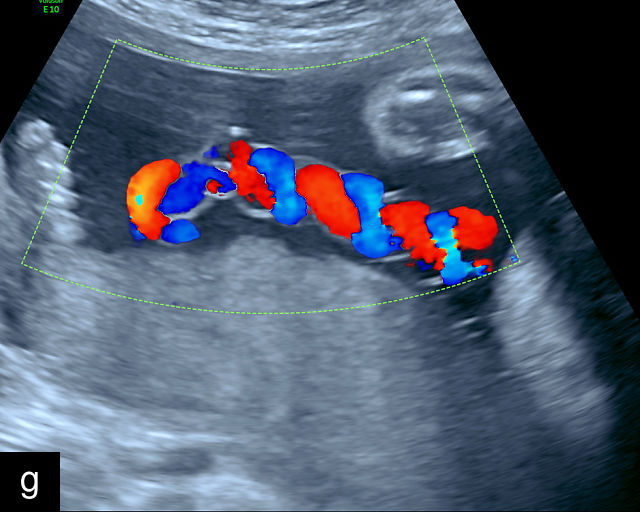

Ultrasound is the primary diagnostic method for identifying VCI. Normally, the cord inserts into the center or edge of the placenta and is fully protected by Wharton’s jelly. In contrast, a velamentous cord insertion is visualized on ultrasound as the cord inserting into the membranes, with unprotected fetal vessels running to the placental margin (Figure 20; Video 11). Color flow Doppler and three-dimensional ultrasound can enhance diagnostic accuracy. Velamentous cord insertion may also occur into the dividing membrane in a multifetal pregnancy (Figure 20e). When unprotected fetal vessels from a VCI cross over the cervix, the condition is termed vasa previa, posing a significant risk of fetal exsanguination if these vessels rupture. Because VCI is a strong risk factor for vasa previa, a color flow Doppler sweep over the cervix is recommended when VCI is identified. If concerns about vasa previa persist, transvaginal ultrasound with color Doppler may be performed for confirmation.30

20

(a–c) Grayscale (a) and color Doppler (b,c) ultrasound images of velamentous cord insertion. The cord inserts into the membranes (arrow), from where unprotected fetal vessels (arrowheads) traverse the membranes to insert into the edge of the anterior (a,b) or posterior (c) placenta (p). (d) Color Doppler ultrasound image of velamentous cord insertion, showing the cord inserting into the membranes posteriorly (arrow), from where unprotected fetal vessels (arrowheads) traverse the membranes to insert into the edge of the anterior placenta (p). (e) Ultrasound with color Doppler showing velamentous vessels (arrow) running through the dividing membrane in a dichorionic diamniotic twin pregnancy. The right image shows the placenta after delivery.

11

Color Doppler ultrasound imaging of velamentous cord insertion. The cord inserts into the membranes from where unprotected fetal vessels traverse the membranes to insert into the edge of the posterior (a) or anterior (b) placenta.

Nomiyama and colleagues conducted a study in which color Doppler screening of placental cord insertion was routinely performed on 587 patients during second-trimester anatomy scans.248 They successfully identified the placental cord insertion in 586 cases (99.8%) and correctly diagnosed five cases of VCI, with one false-positive result.248 The study reported a sensitivity of 100%, specificity of 99.8%, positive predictive value of 83% and negative predictive value of 100%. However, the study population in Japan had a significantly lower average body mass index (BMI) compared to populations in the Western world. Increased BMI, fetal position, uterine fibroids and posterior placenta may hinder visualization of the cord, making these results less generalizable to populations with higher BMI prevalence.

Sepulveda and colleagues evaluated 832 patients during the second and third trimesters using color Doppler and successfully visualized placental cord insertion in 825 cases (99%), diagnosing seven cases of VCI.249 These authors, in a separate study, also screened 533 pregnancies during the first trimester and correctly identified five cases of VCI.250

In the USA, consensus guidelines recommend assessing placental cord insertion during the second-trimester anatomical ultrasound examination when feasible. This approach is being increasingly recommended in other countries.251 At our center, this assessment has been routinely performed as part of the second-trimester anatomy scan for several years, and we strongly advocate for its inclusion as a standard component of the examination.